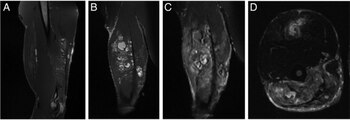

La resonancia magnética que se le realizó arrojó como resultado la presencia de quistes en sus músculos. Finalmente, el hombre confesó: había inyectado aceite de coco en su bícep derecho. Creía que de esa forma los glóbulos grasos aumentarían mientras esperaba que su tendón sane. Sin embargo, el aceite produjo una coagulación lo que provocó una lesión proteica.